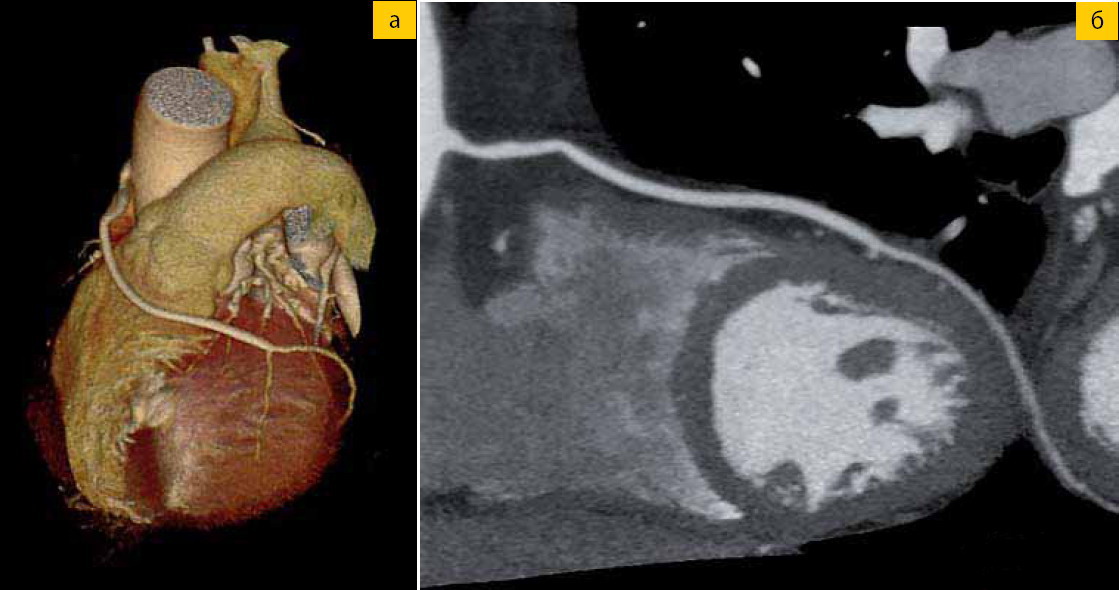

Наблюдение 4 Рис. 4 а-б. Пациент с венозным шунтом (трехмерное изображение и многопроекционная реконструкция)

Наш первоначальный опыт исследования более чем 100 пациентов показал, чтообеспечивает превосходное качество изображений (рис. 1—4). Для всех исследованных нами пациентов та информация, которая была получена во время сканирования, помогала в дальнейшем при принятии клинических решений, а количество «холостых» исследований (не использовавшихся для диагностики) оказалось практически нулевым. компьютерный томограф AquilionONE